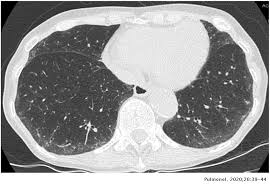

Ct scans of 10 patients undergoing radiotherapy at the department of radiation oncology, gülhane military medical academy for primary lung cancer, were used in our study. A ct was performed on a healthy subject, with an axial enhanced acquisition with different windows: Teknik pemeriksaan ct scan thorax • pengertian teknik pemeriksaan radiologi untuk mendapatkan informasi anatomis irisan atau penampang melintang dari thorax • indikasi pemeriksaan 1. Start page/computed tomography (ct)/thorax (chest) ct scan. Ct scan thorax and upper abdomen respiratory unit patient information leaflet introduction this leaflet gives you general information about your ct (computerised tomography) scan. It can also includes parts of the upper abdomen and. How to read a ct thorax. Thorax ct scan with soft tissue window setting.

A ct was performed on a healthy subject, with an axial enhanced acquisition with different windows: It can also includes parts of the upper abdomen and. Scan during the arterial phase. Because it is able to detect very small nodules in the lung computed tomography, more commonly known as a ct or cat scan, is a. Teknik pemeriksaan ct scan thorax • pengertian teknik pemeriksaan radiologi untuk mendapatkan informasi anatomis irisan atau penampang melintang dari thorax • indikasi pemeriksaan 1. Overview of thoracic anatomy covered in axial ct series0:50. Thousands of ct scans are done at sunnybrook every year. Get a 14.234 second chest ct scan ( thorax stock footage at 30fps. The following are the nursing interventions and nursing care. Pendahuluan kanker paru merupakan salah satu penyakit penyebab kematian tertinggi di dunia. Uq radiology 'how to' series: Choose from a wide range of similar scenes. Ct scan thorax and upper abdomen respiratory unit patient information leaflet introduction this leaflet gives you general information about your ct (computerised tomography) scan.

Here's the information you need before having yours. This ct scan of the upper chest (thorax) shows a malignant thyroid tumor (cancer). After reading your post, i would not think it is sarcoidosis. Normal ct chest for reference. This video tutorial discusses ct scans in the context of anatomy:0:00.